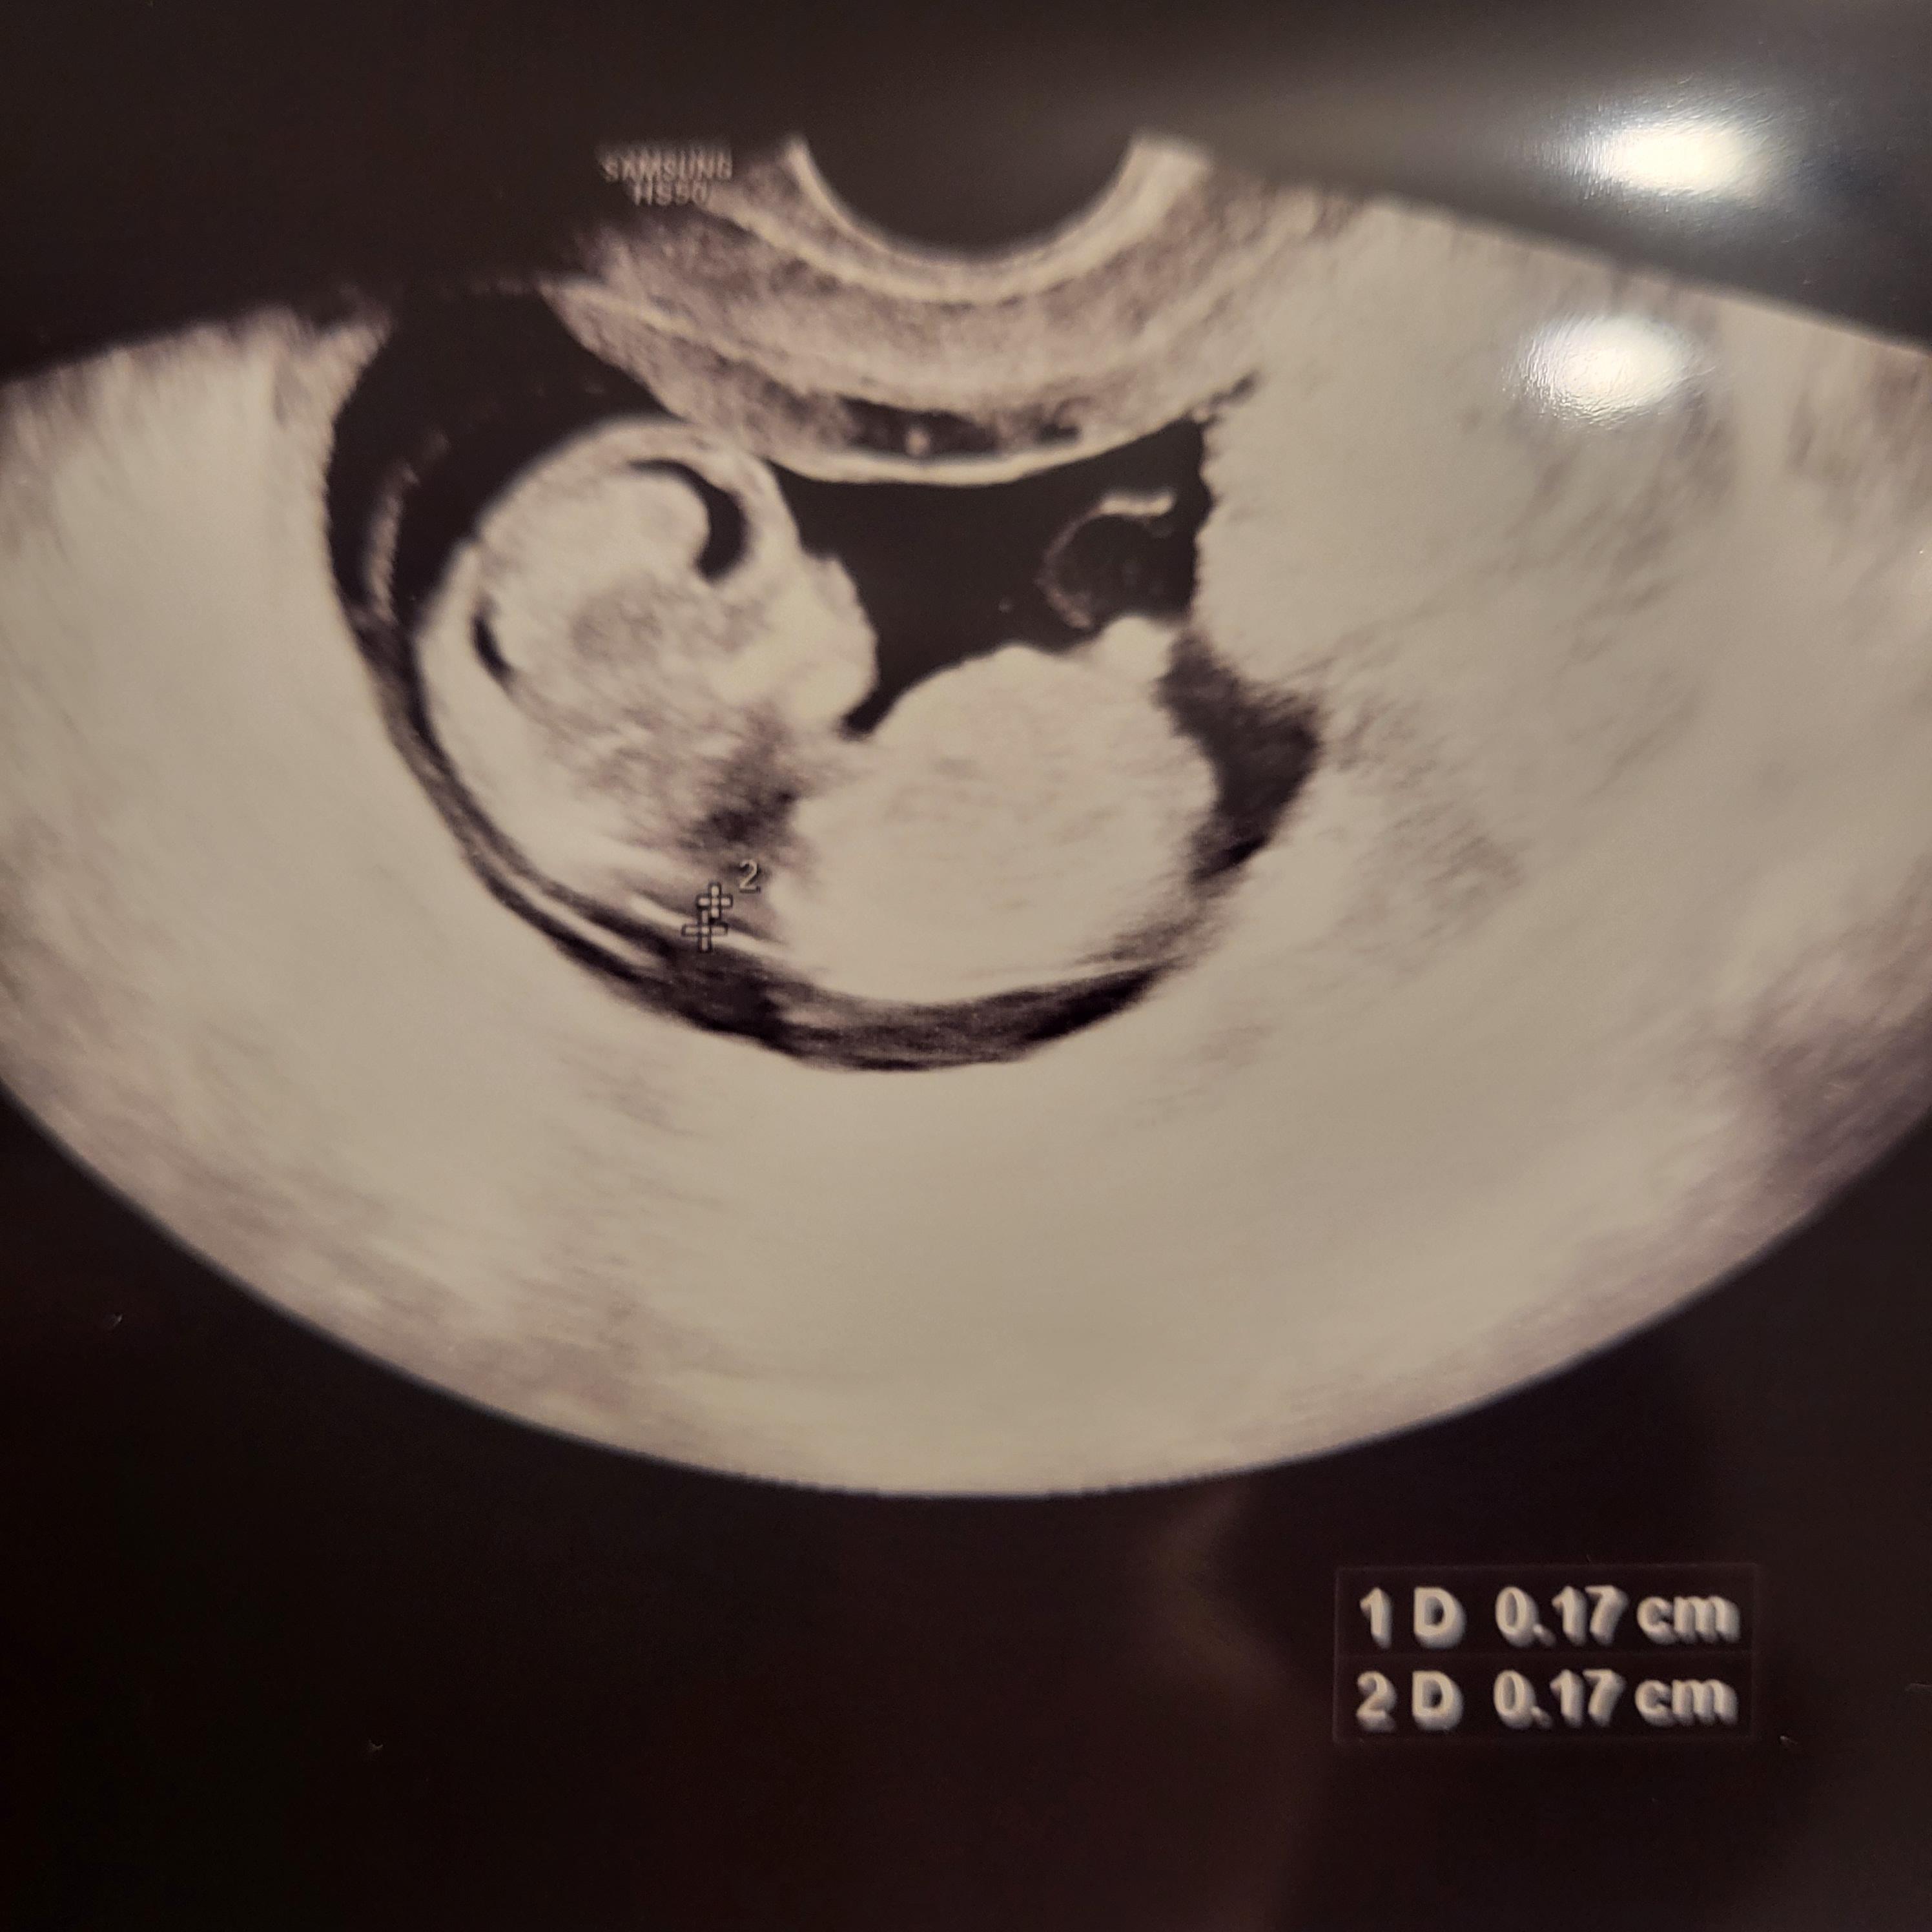

아기의 크기는 정밀 초음파로 측정되었습니다. 아직 12주가 되지 않아서 조금 작게 느껴졌어요.

병원을 방문할 때마다 임신 날짜는 11주 5일과 12주 0일 사이에 다양했습니다.

마지막 월경일을 기준으로 12주 0일입니다.

아기 집을 확인한 날을 기준으로 11주차와 5주차입니다.

질 초음파는 아기를 명확하게 보여주었습니다.

그는 재빨리 넥 포일만 확인했고 0.17cm에서 안전한 판독값을 측정했습니다.

휴 행운을 빕니다, 감사합니다!